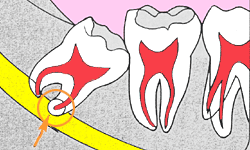

親知らずは20歳前後に生えてきます。現在60歳の私は上の親知らずは虫歯になったので25歳の頃に抜歯してもらいました。下の親知らずは2本とも横に向いて半分生えている状態ですが、抜くのが怖いので、頑張って虫歯にならないように1日5回以上全体の歯を磨いています。私は口腔外科出身なので口腔外科の7年間とその後5年間ぐらいの期間に1,000本以上は抜いてきましたが、現在は済生会千里病院(南千里)に紹介状を書いて抜いてきてもらう事にしています。年間30人ほどは紹介させて頂いています。ご希望があれば紹介状をお書きします。

下は神経に触ると「唇のしびれ」や「唇の周辺の知覚麻痺」が起こるので、やはり現役の口腔外科の先生の方が安心だと私は思います。私も口腔外科で多くの患者さんを診させてもらい、安全の教育を最優先に受けたこともあり、患者さんの安全を優先し当院では無理はしないことにしています。